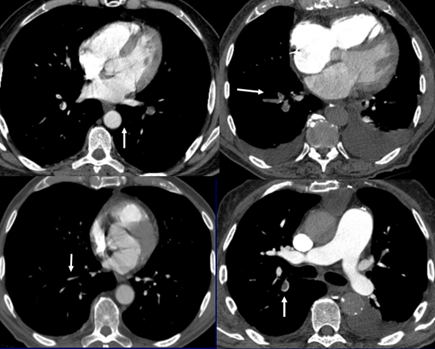

Imagen 4.

Imagen 4

Angiotomografía simple y contrastada de tórax.

Reporte: Los hallazgos son compatibles para TEP crónico.

Signos Directos: Defecto de repleción arterial completo. Defecto de repleción parcial. Bandas entrecruzadas.

Signos indirectos: Calcificaciones del trombo. Hipertensión pulmonar. Patrón en mosaico. Aumento del calibre de las arterias bronquiales y colaterales.